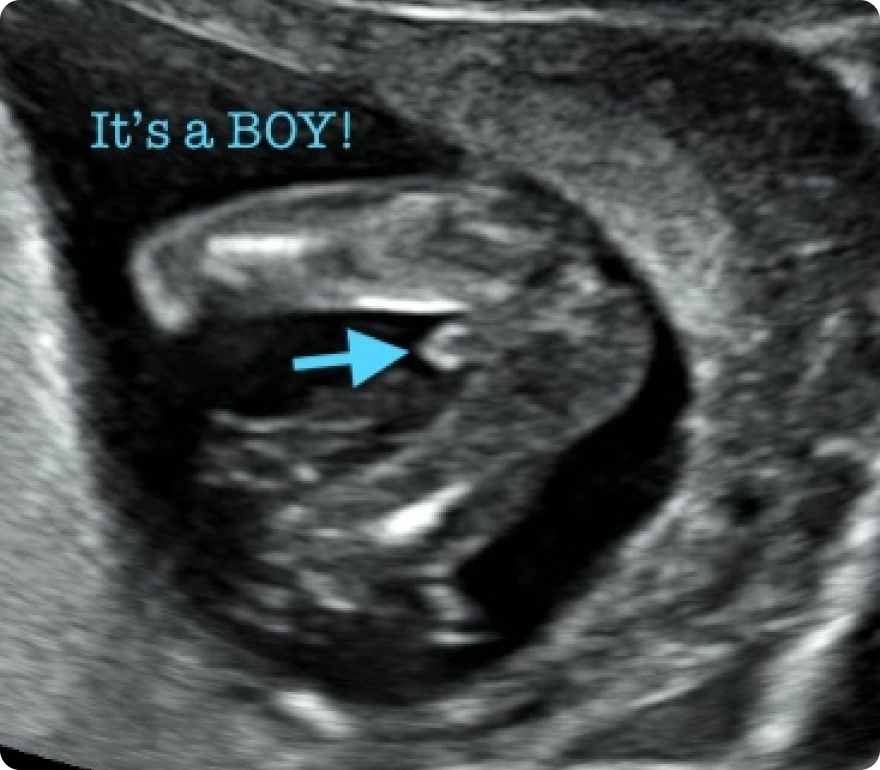

When it comes to gender determination, we create an experience you will never forget. Your reveal is paired with enchanting music and a magical light show that illuminates the entire room in pink or blue, celebrating the beginning of your baby’s journey.

3D

Detailed still images capturing your baby’s facial features, fingers, and toes with depth and clarity beyond 2D scans.